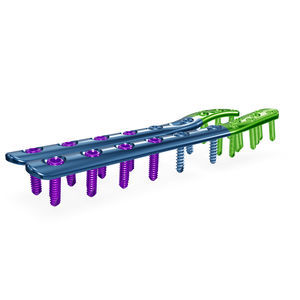

2.7/3.5mm JY Locking Compression Plates for Tibia/Fibula Titanium, low profile, pre-contoured plates in a variety of shapes for various types of tibia and fibula ...

... with varying bone quality. Titanium, low profile, pre-contoured plates in a variety of shapes for various types of tibia and fibula fractures. Specifically designed for reduction, compression, ...

The SurgTech Trauma System is a plate and screw fixation system. Plates and screws are offered in “mini”,“small” and “large” set sizes in a variety of shapes based upon the anatomical fixation required. Features It ...

The SurgTech Trauma System is a plate and screw fixation system. Plates and screws are offered in “mini”,“small” and “large” set sizes in a variety of shapes based upon the anatomical fixation required. Features It ...

The Fibula Locking Plate is a proven osteosynthesis system for various distal fibula fractures. The special feature of this implant is the free choice of screw placement. The user is ...